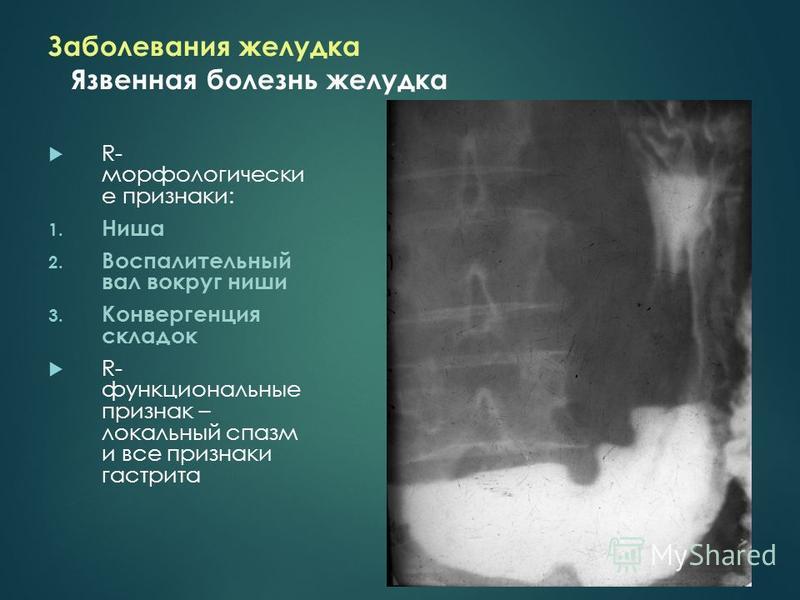

Современные технологии в медицине: рентгенодиагностика заболеваний желудка